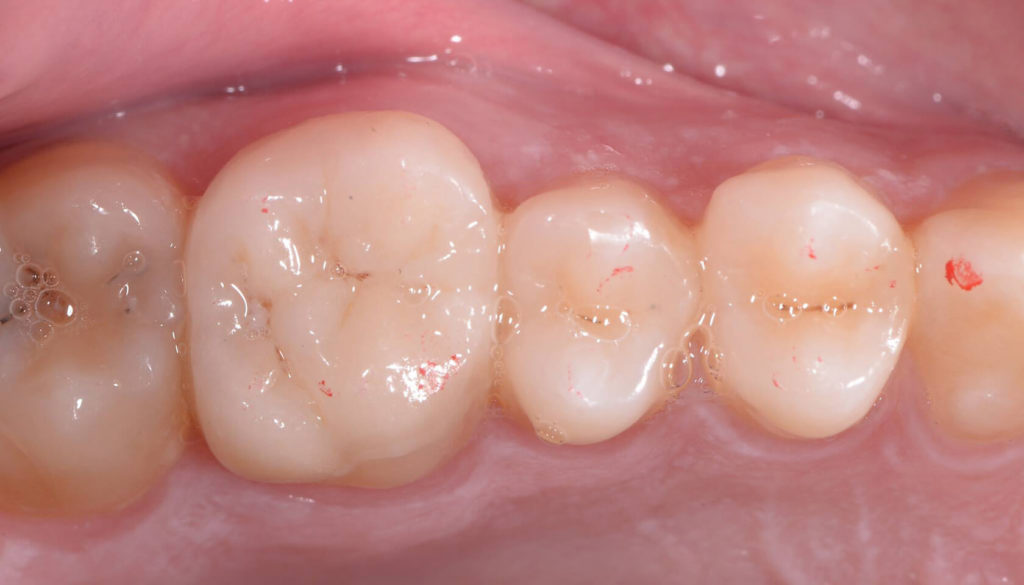

Patient presented with deep distal decay on first molar. Used deep margin elevation and papillectomy. No attempt was made to establish 3 mm biologic width space. Overlay prep and lithium disilicate indirect restoration placed. Photos from 15 month follow up included.